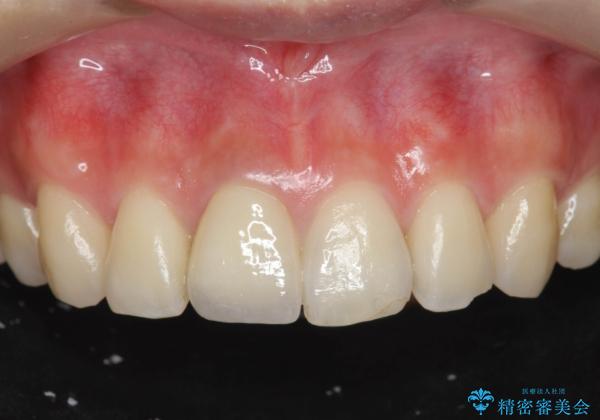

自然な色調をセラミッククラウンで再現することができ、審美性の改善に大変喜んでいただくことができました。